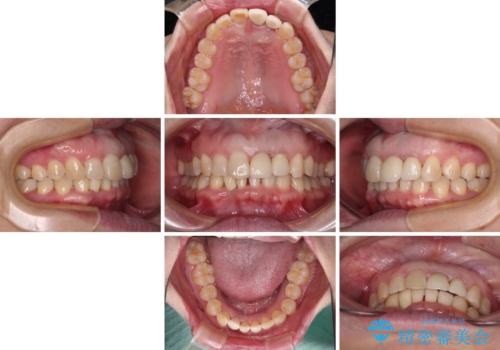

- 下顎前歯が抜けそうとのことで来院された患者様です。

初診の状態ではすぐにでも抜けそうな状態で、インプラントによる補綴治療を行うこととしました。

インプラント治療に際し、前歯の叢生に対する矯正治療を提案したところ、興味を持たれたので、インビザライン・ライトによる矯正治療を行うこととしました。

抜歯後にスペースができると恥ずかしいため、抜歯した歯を接着剤で固定した上で矯正治療を行い、その後インプラントやオールセラミッククラウンの装着を行うこととしました。